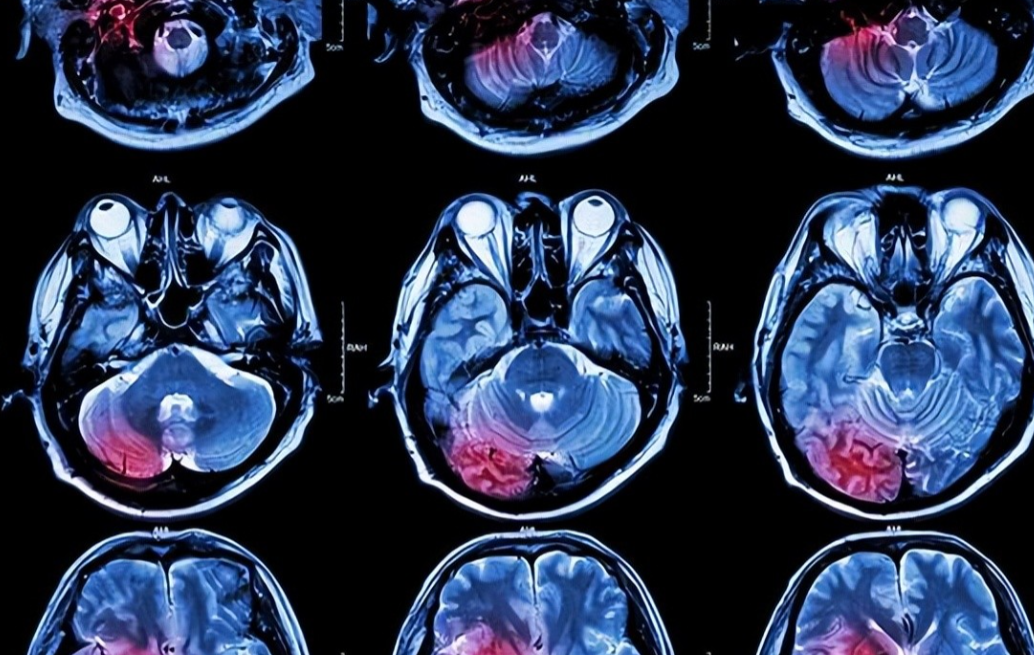

在对抗脑肿瘤的长期探索中,化疗始终是不可或缺的治疗手段。其中,胶质母细胞瘤(GBM)作为恶性程度最高的类型,治疗难度尤为突出。血脑屏障(BBB)作为中枢神经系统的天然保护屏障,由致密的毛细血管内皮细胞、星形胶质细胞足突及基底膜构成,可精准调控物质跨膜转运,却也成为多数化疗药物难以逾越的递送障碍,极大限制了治疗效果。

脑肿瘤治疗的首要挑战,在于如何突破药物向脑组织的递送障碍。血脑屏障的磷脂双分子层结构,对药物的脂溶性提出了严苛要求——脂溶性越高,越易通过被动扩散进入脑组织。